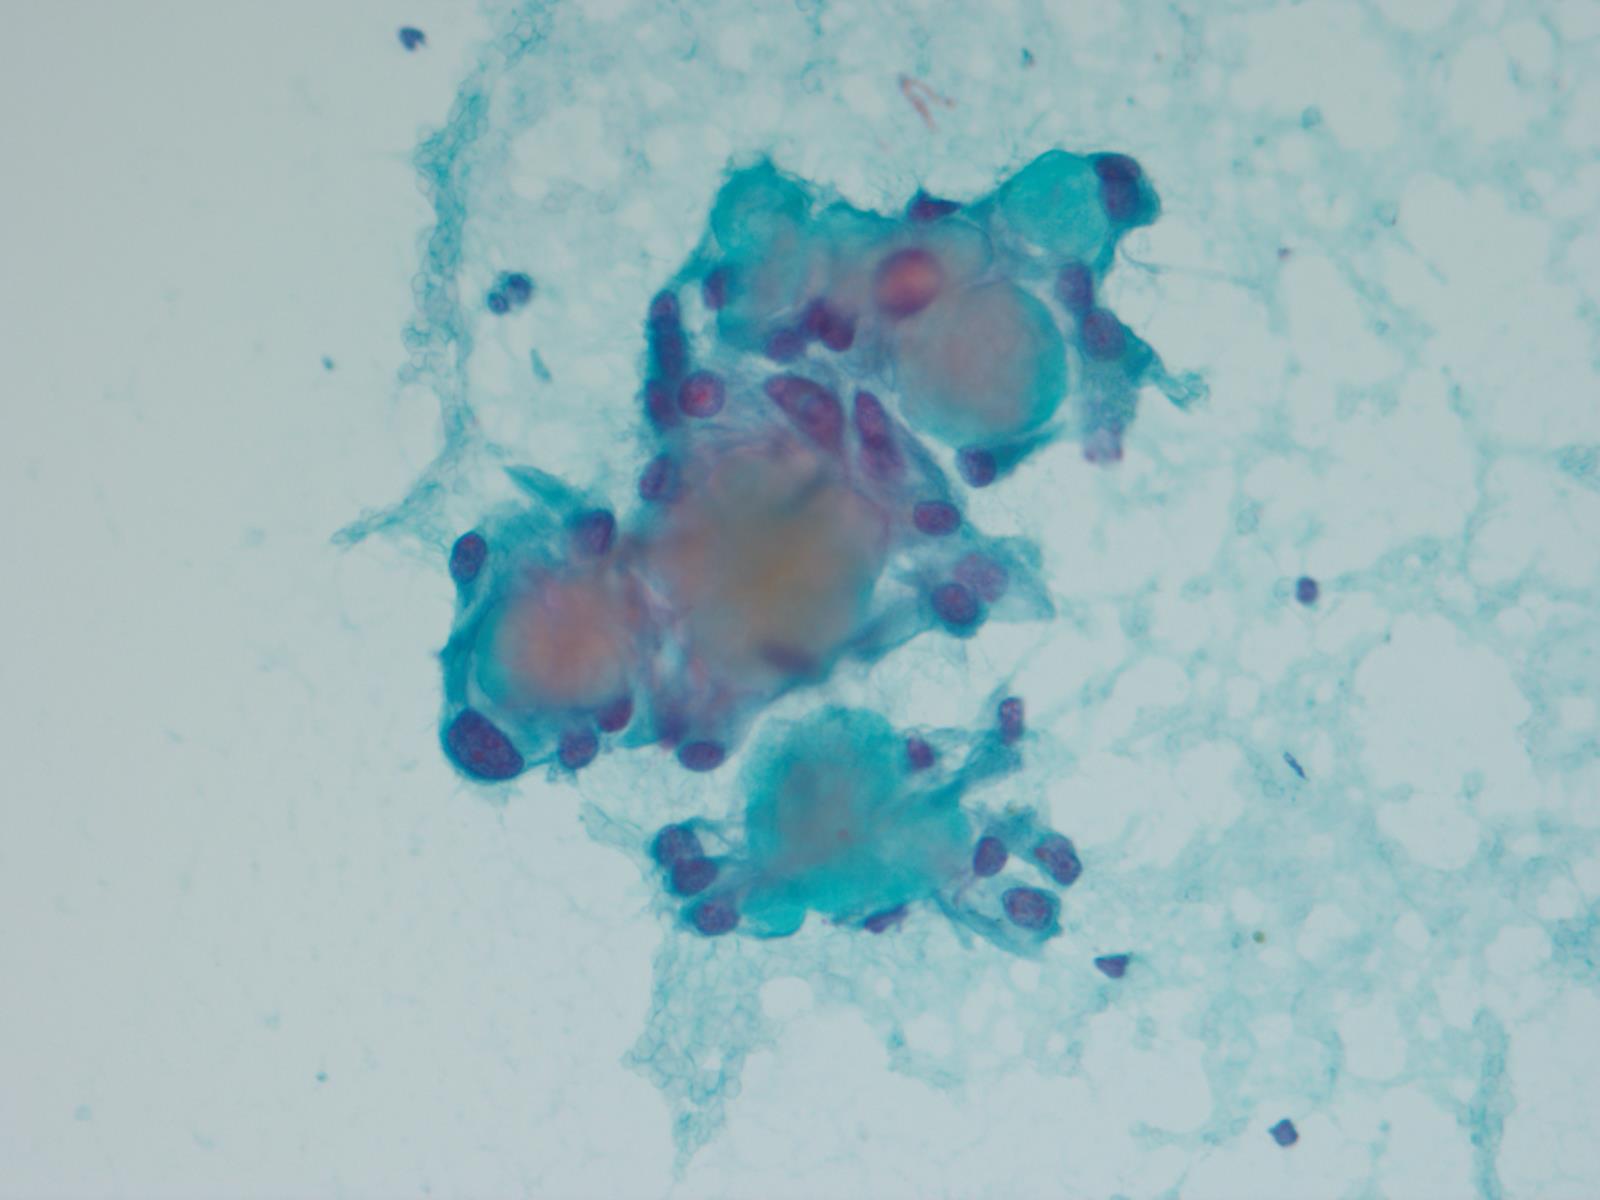

Cytology description

- Cytology usually recapitulates the histologic findings; myxoid matrix and cells show nuclear uniformity and process formation

- Epithelioid to spindle cells

- Arrangement of tumor cells around blood vessels forms papillary structures with perivascular myxoid change

- Tumor cells are arranged around myxoid microcysts

Cytology images